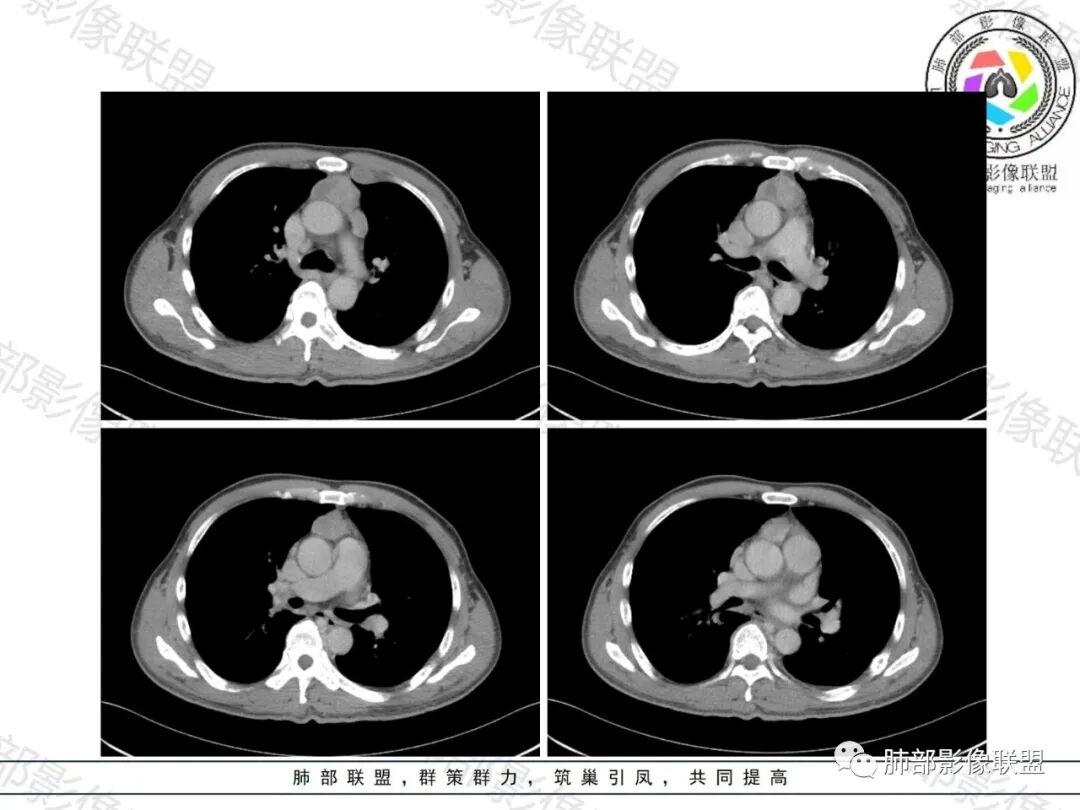

一切∮随缘: 前纵隔一实性肿块,居中,延主动脉、肺动脉间隙生长,病变较软,包绕血管,平扫密度均匀,增强后均匀强化,椎体有骨质破坏,考虑:胸腺癌(鳞癌,类癌强化偏弱),胸腺瘤,淋巴瘤,转移瘤。

必有路:男性,体检发现,前纵隔肿瘤,CEA轻微高,肿瘤对血管侵犯不明显,可疑上腔受侵犯,轻度强化,椎体破坏,考虑胸腺癌与淋巴瘤鉴别,鉴于CEA增高,胸腺癌>淋巴瘤,建议活检。

陈学君: 前纵隔肿块,多结节融合状,轻度强化,色绕左头臂静脉,伴有椎体骨质破坏,CEA轻度升高,综合考虑淋巴瘤。

看图说话: 前上纵隔实性肿块,密度均匀,均匀强化,包绕血管,受压不明显,胸椎体骨质破坏,考虑恶性:胸腺瘤,淋巴瘤,转移瘤。

不吝慷慨: 考虑恶性,有侵袭性并有胸椎转移性骨质破坏,常规胸腺癌。病灶结节状,似有结节融合表现,淋巴瘤也不能排除。再来个异位甲状腺癌也不意外。

张小兵: 前纵隔肿块,多结节融合,内乳淋巴结及纵隔淋巴结肿大,未见坏死,骨质破坏,恶性,淋巴瘤可能。

飞鹰行动: 老年人,男性,前上纵隔肿块,病灶相互融合,增强轻度强化,包绕周围血管生长,胸壁可见软组织肿块,形态规则,密度均匀,呈肉包骨样改变,部分椎体骨质破坏,CEA轻度升高,综合考虑小圆细胞类肿瘤,淋巴瘤,其次胸腺瘤,转移瘤。

小兜: 男,55岁,体检发现纵隔占位,CEA轻度增高,LDH明显增高。CT示前纵隔占位,多结节融合,包绕大血管生长,未见明显血管侵犯,平扫密度较均匀,增强扫描轻度强化,伴有骨质破坏吸收,首先考虑淋巴瘤,其次胸腺癌,(CEA增高,降钙素不知道怎么样,有增高再考虑一个甲状腺髓样癌)

琦遇: 前纵隔占位,包绕大血管,侵犯血管,纵隔淋巴结以及左侧内乳淋巴结肿大,病灶不规则,分叶,强化不明显,胸椎及肋骨转移,考虑SCLC 、鳞癌、淋巴瘤、转移(甲状腺癌转移)。结合临床首先考虑SCLC。

红星: 前纵隔分叶状的实性肿块,密度比较均匀,部分沿着血管间隙包绕血管,并深入到胸廓入口处,增强扫描轻度强化,可见片状的不均匀强化,主动脉弓旁及纵隔内见多发的淋巴结。椎体见骨质破坏。考虑淋巴瘤?特点是多结节融合,多发病灶范围比较广,具有包绕血管的征象,强化中等。鉴别:胸内甲状腺瘤?转移瘤?胸腺的恶性占位?

King:前中纵隔多结节融合感肿块+骨破坏+内乳淋巴结+叶间裂可疑微结节+LDH偏高,恶性,考虑小细胞癌和淋巴瘤,再查NSE和胃泌素释放前肽。从年龄和骨的角度,更偏向小细胞。

刘丹: 前纵隔融合成团软组织肿块,胸椎骨质破坏,增强轻度强化,部分包绕血管,考虑淋巴瘤,鉴别胸腺及甲状腺肿瘤。

毛勤香: 前纵隔实性占位,融合分叶状,左侧内乳淋巴结肿大,轻度强化,椎体骨质破坏,考虑恶性,首先考虑淋巴瘤,鉴别鳞癌。

采莲: 中年男性,前纵隔正中肿块,有分叶,密度不均,周围有淋巴结肿大,包绕血管,内乳动脉增粗,纵隔有肿大淋巴结,胸椎有骨质破坏,查体发现,CEA轻度升高,考虑恶性,淋巴瘤可能性大,鉴别胸腺瘤。

空格: 恶性无异议!抛开纵膈主灶,肺内以两侧斜裂局限弥漫增厚,小结节主要分布在水平裂周围,左下肺纹有串珠状改变,单以肺内分析,淋巴道受累为主。脊柱及肋骨的改变,常见于转移灶,骨淋巴瘤什么样不太熟悉。纵膈内前纵膈为主,腔静脉后也有,位置比较高,形态结节状,部分融合,没有明确的坏死,强化也较均匀,这几点似乎淋巴来源大于胸腺。所以淋巴来源排前面,到底是原发淋巴瘤,多部位侵润,还是猪脚没出场,躲在腹部,胸部都是转移灶?需要腹部检查后决定。患者体重无减轻,主角在腹部的可能性非常小了,主角应该都在台面上了。脊柱的改变,是淋巴瘤的命门。

良孑: 前纵隔肿物,位置居中,边界清,密度均,冠状位重建肿物与右侧颈部软组织肿物相连,中度强化,血管包饶及飘浮,推体及局部肋骨骨质破坏,定性恶性,支持淋巴瘤或胸内甲状腺。

1.中年男性,体检发现。CEA轻度增高

2.前纵隔不规则块影,密度均匀,有多结节堆积融合感,边界隐约可辨,轻度不均匀强化。3.块影包埋并挤压左无名静脉。相邻大血管均未见侵犯,纵隔两侧胸膜未见突破,未见胸腔积液,右侧叶裂结节样增厚。

4.左内乳淋巴结肿大,上纵隔及右颈根部淋巴结肿大。

5.胸椎及肋骨见虫噬样吸收破坏,骨皮质不完整,未见硬化,骨旁软组织影增宽,未见死骨。

1.胸腺所在地不规则块影,有多结节堆积融合感,淋巴结肿大,胸椎骨及肋骨破坏,恶性肿瘤判断当无异议。

2.块影边界可分辨,不似一般胸腺癌那样攻城略地或糊成一片,也没有胸水。

多结节堆积融合感,内乳淋巴结等肿大,似乎提示我们更像是淋巴瘤,淋巴瘤界外浸润骨骼并不少见。

3.黄勇老师曾发现胸腺类癌易转移至胸椎,本例病理报告恰恰为胸腺类癌。